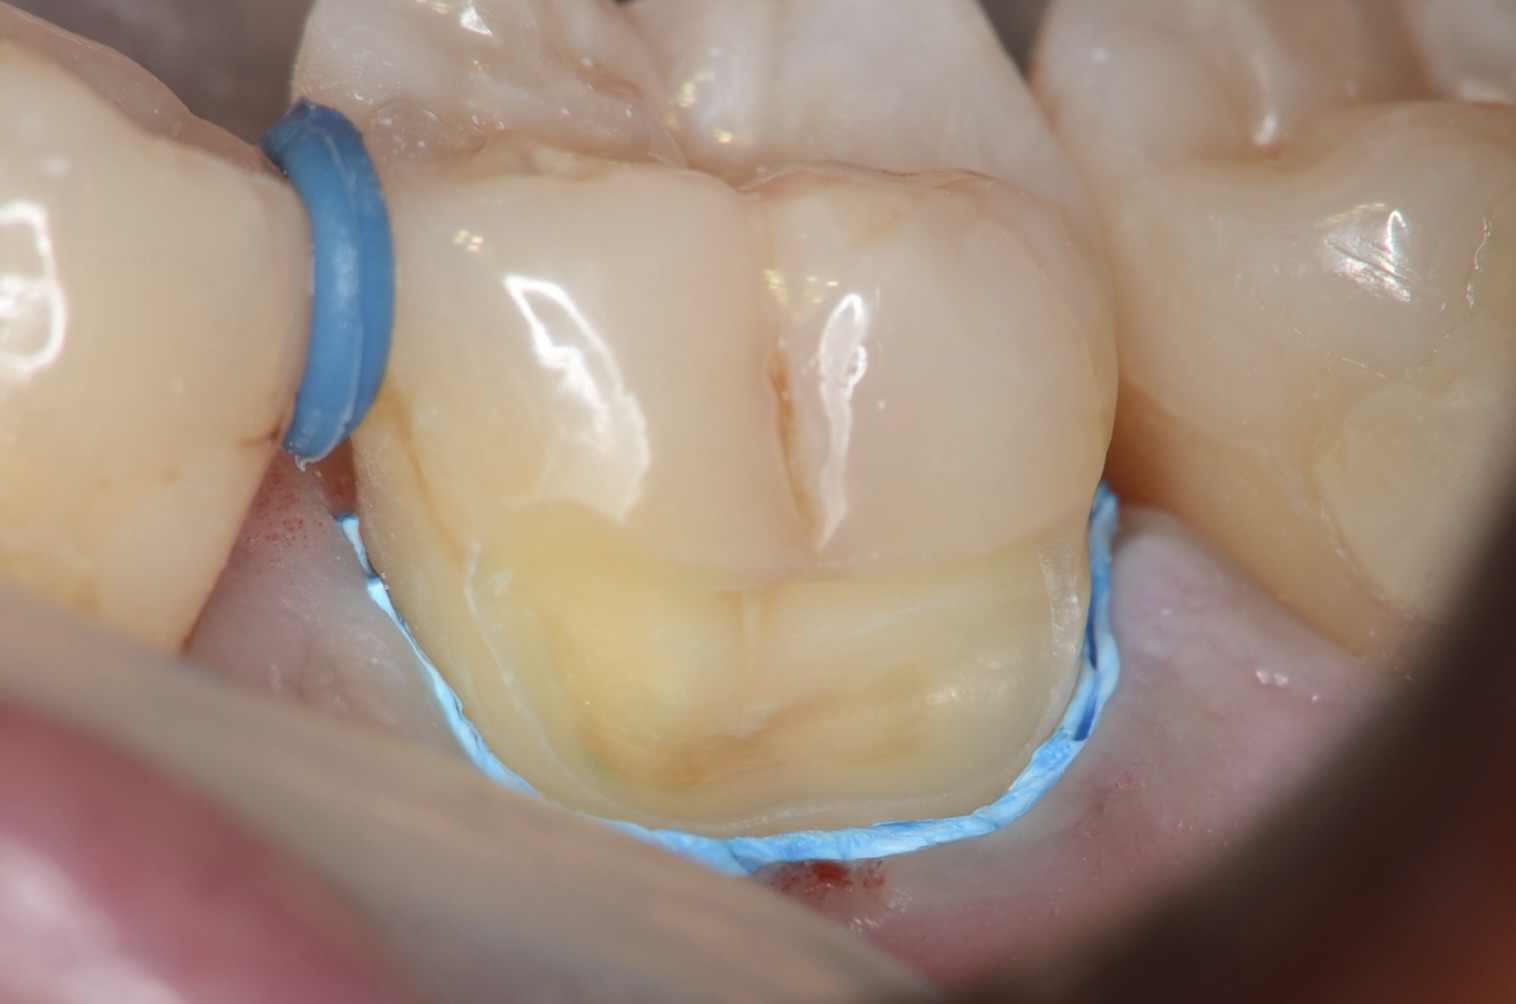

レジン充填

フロワブルレジンを用いて、その表面張力を利用して滑らかで段差のないレジン充填を実現させます。 -